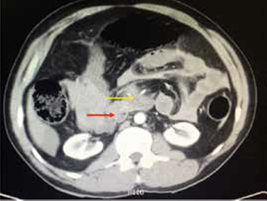

En la figura 1 se esquematiza la conducta tomada en los 62 pacientes a quienes se les practicó TC. En 14 pacientes, se indicó la cirugía por los hallazgos de la tomografía: en 5, las lesiones estaban localizadas en la cara anterior del abdomen, en 4, en la zona toracoabdominal izquierda, en 2, en la cara posterior del abdomen, en 2, en el flanco izquierdo, y en 1, en la pelvis. Los hallazgos tomográficos que sugerían lesión en este grupo de 14 pacientes fueron, en orden de frecuencia, trauma de órgano solido con sangrado activo (28,5 %), perforación del tubo digestivo (28,6 %), ruptura del diafragma (7,1 %) y trauma vascular (7,1 %) (figuras 2 y 3). Los hallazgos tomográficos y quirúrgicos en ellos se muestran en la tabla 1.

En este mismo grupo de 14 pacientes operados, 12 tuvieron lesiones que requerían manejo quirúrgico; en dos (el 4 y el 8), la laparotomía no fue terapéutica (figuras 4 y 5); en tres, el abdomen no se pudo evaluar, aunque había estabilidad hemodinámica, por lo cual se les practicó TC; el número 1 tenía politrauma, llegó intubado y sedado a la institución, al igual que el número 12; el número 2 tenía trauma raquimedular asociado.